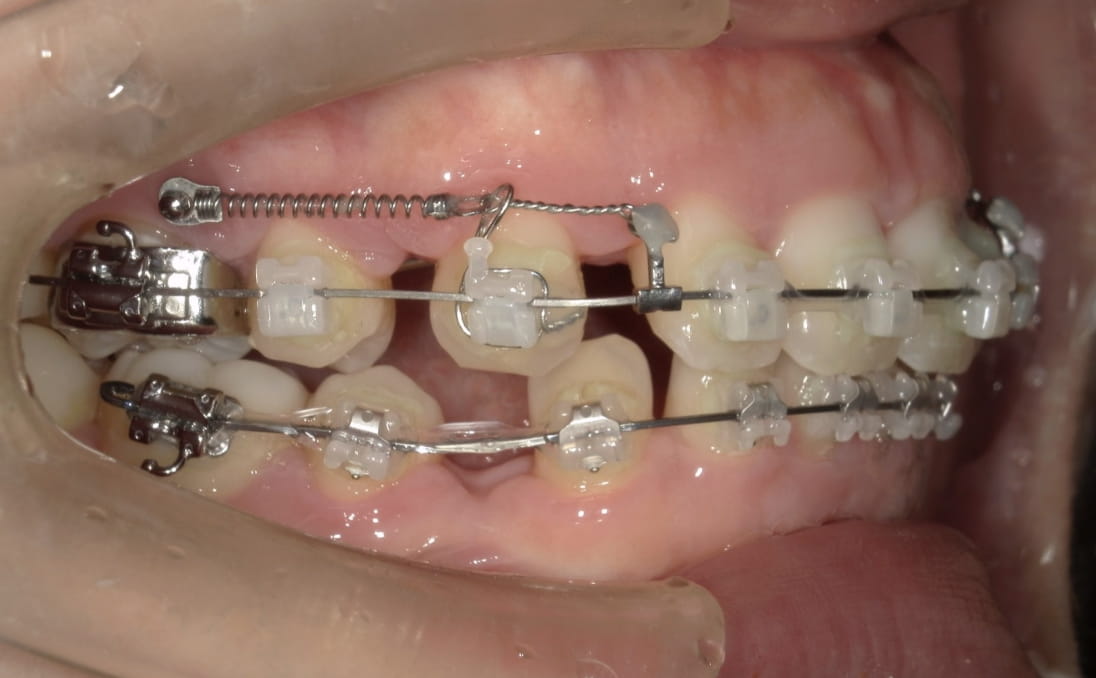

治療装置 ハーフリンガル矯正(上顎裏側・下顎表側)

抜歯 抜歯あり

診断名 上下顎前突(口ゴボ)

副作用 歯肉退縮・歯根吸収・歯髄・壊死・癒着による予期せぬ歯の動き

上下顎ともに裏側で装置を完全に隠しながら、アンカースクリューで前歯をしっかり後退。見た目と仕上がりを両立した症例。

治療前

治療中①

治療中②

治療中③

治療後